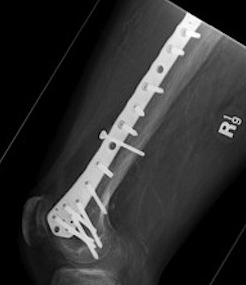

Lateral plate

Retrograde IM nail

MIPO plate technique

- percutaneously elevate muscle off femur with elevator

- insert appropriate length plate (4 bicortical screws above)

- second proximal incision

- obtain indirect reduction

- attach plate with screws